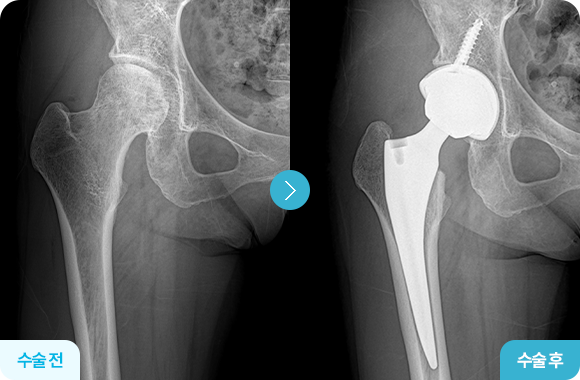

인공 고관절 치환술 전후사진

인공 고관절 치환술

고관절은 퇴행성 변화나 골절로 연골이 닳고 뼈가 손상되면,

단순한 통증을 넘어 관절 자체의 기능이 사라지게 됩니다.

이 단계에서는 약물이나 물리치료로는 회복이 어렵기 때문에,

손상된 뼈와 연골을 인체에 안전한 금속, 세라믹 재질의 인공관절을 삽입하는

인공 고관절 치환술을 통해 관절의 기능을 되살리는 치료가 필요합니다.

특히 대퇴경부 골절의 경우, 혈류가 차단되면 시간이 지나며 대퇴골두 괴사가 진행될 수 있어

조기 회복을 위해 인공 고관절 치환술을 진행하게 됩니다.